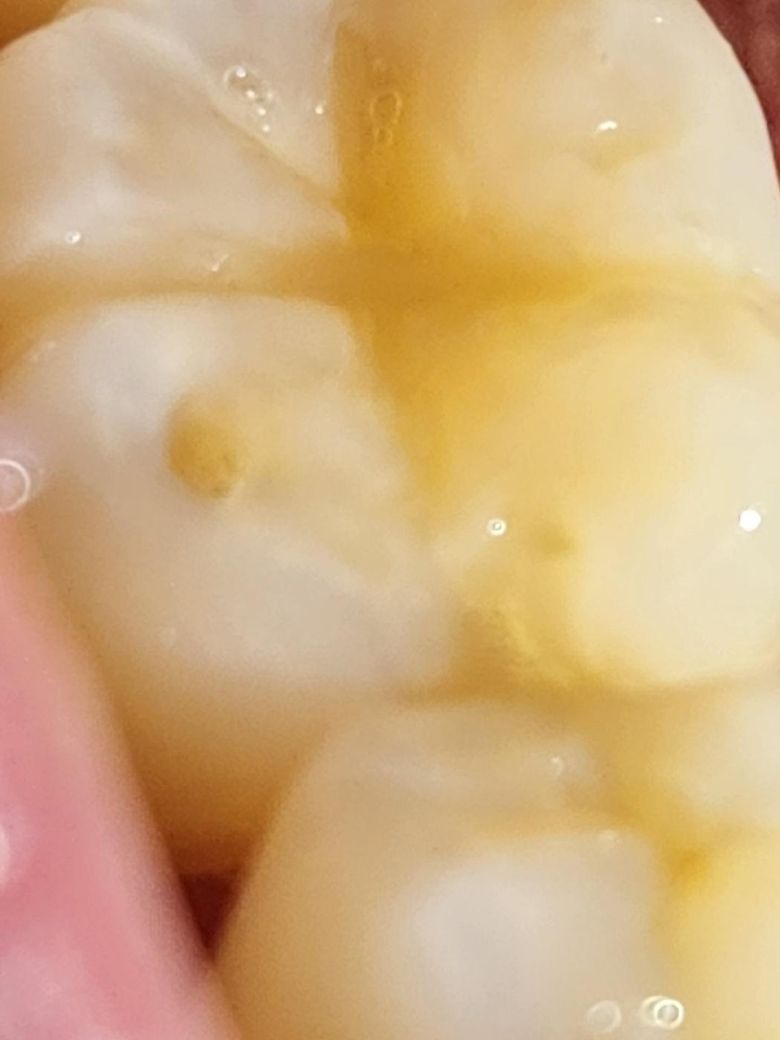

이빨에 구멍이 살짝 났는데 메꿔야 하는걸까요?

치과의사님들 밥먹다 깨진건지 충치는 아닌거같은데 놔둬도 될정도인지 아니면 메꾸는게 나을지 의견부탁드립니다..ㅠ

만약메꿔야되면 구멍이 좀커지겠죠..?

치아가 마모되어 그런 것으로 보입니다. 해당 부위 음식물이 잘 끼어 충치가 생기기 쉬우니 메꿔주시는 게 좋습니다.

지하의 구멍이 나게 되면 해당 부위에 이물질이 낄 수 있습니다. 이물질이 자주 끼게 되면 충치가 생길 수도 있으니 이물질이 끼는 부분은 치과용 재료로 충전을 해주는 것이 좋습니다.

자세한 확인을 위해서 치과에서 진료를 받아보는 것을 권유드립니다.

사진에 보이는건 치아가 교합되면서 자연스럽게 된거라면 치료를 할 필요는 없지만, 깨졋다면 다시 메꾸시는게 좋습니다.

충치 가능성도 있어보입니다 사진으로 봐서 명확하진 않지만 안쪽이 푸석푸석한 양상이 느껴집니다